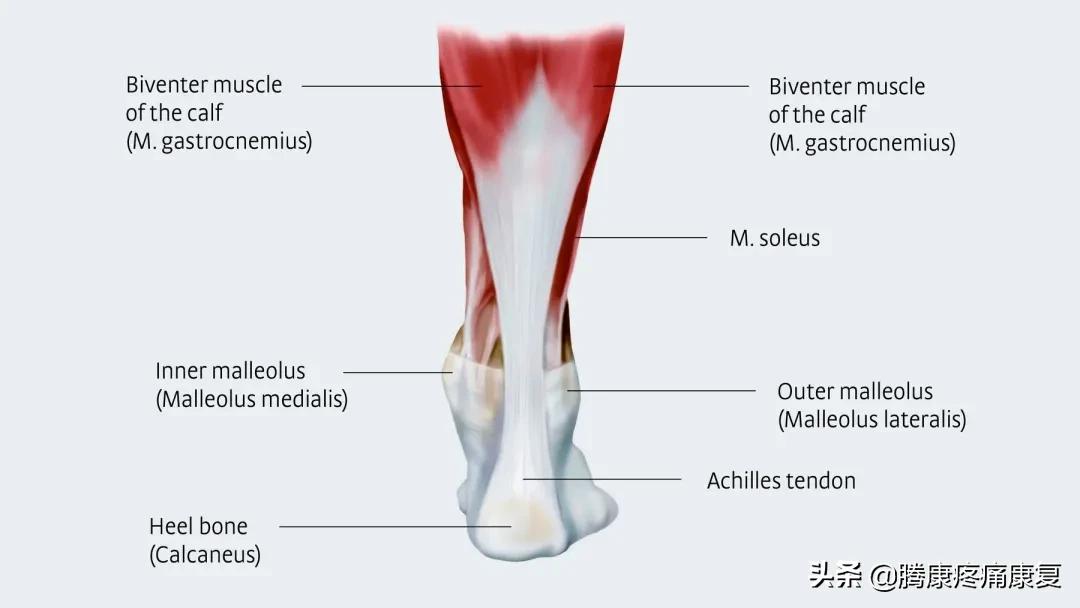

跟腱的解剖

跟腱是小腿三头肌,即腓肠肌和比目鱼肌的肌腹下端移行的腱性结构,止于跟骨结节,是人体最粗最大的肌腱之一,对机体行走、站立和维持平衡有着重要的意义。

由于跟腱的横断面较肌肉组织小的多,约1:60左右,故而跟腱组织负担的单位张力远高于肌肉。